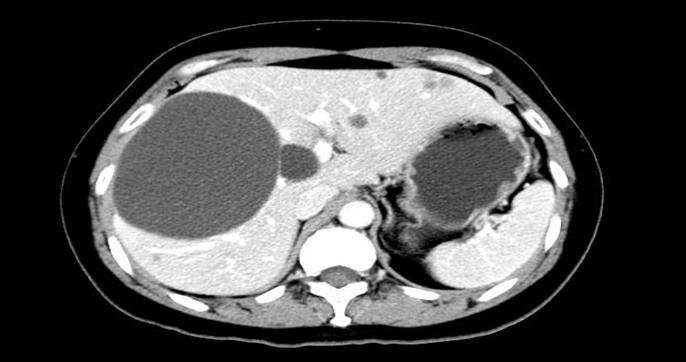

肝囊肿:分为单纯性肝囊肿及多囊肝,是最常见的肝脏囊性占位,单纯性肝囊肿增长缓慢,而多囊肝常合并多囊肾,影像学检查具有典型特点;

图中黑色圆形病灶为肝囊肿